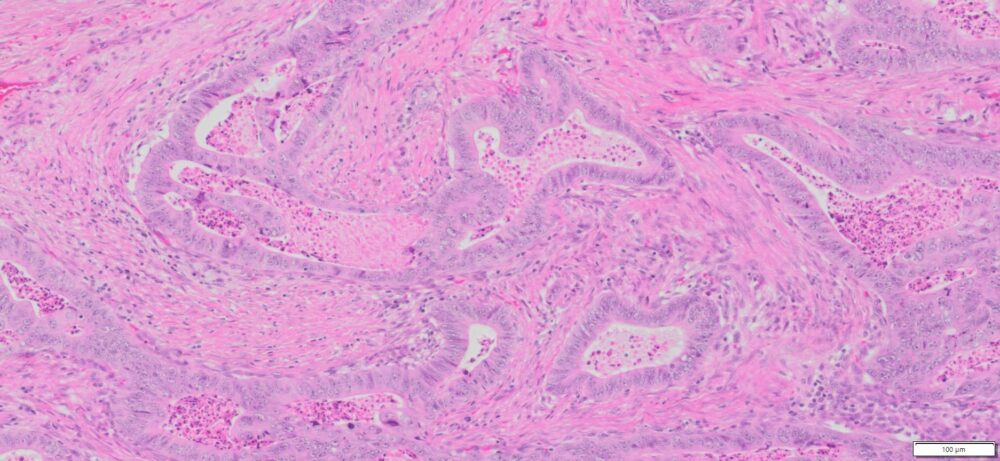

Description

| Tissue | Pathology Diagnosis | Gender/Age (year) | % Tumor area | Tumor Grade | TMN Stage | IHC Data |

| HumanRectum | Moderately differentiated adenocarcinoma of the Rectuma | Female/59 | 45% | II | pT3pN1bpMx | MLH-1,MSH-2,MSH-6 and PMS-2: Preserved nuclear Staining |

Images for H&E Stain and IHC